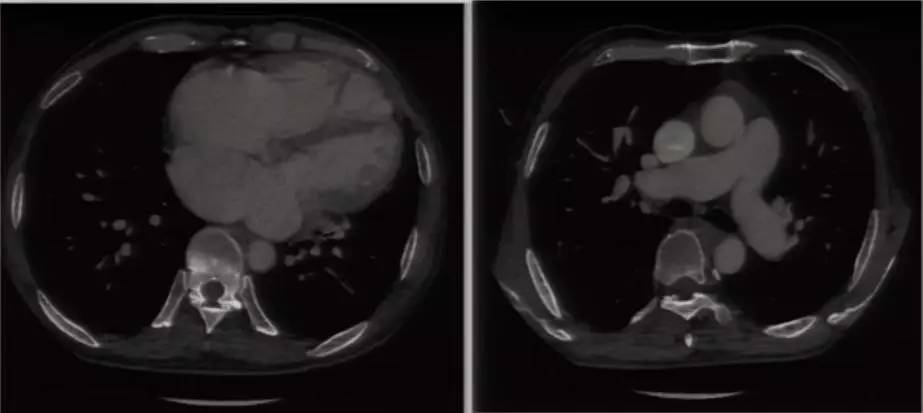

进一步完善相关检查:胸片提示双肺淤血,肺血增多,升主动脉及主动脉结增宽,肺动脉段平直,全心增大,心胸比0.63(图6)。复查超声心动图可见LA 58 mm,LV 53 mm,LVEF 60%,RV 41 mm;房间隔卵圆孔回声分离3 mm,后下部薄弱,探及数处回声脱落,大者约18 mm;二尖瓣前叶发育异常,收缩期瓣体向左房弯曲,致对合不拢。超声提示先天性心脏病(先心病)、Ⅱ孔型房间隔缺损(多发)、卵圆孔未闭、房水平左向右分流 ,二尖瓣脱垂并中大量反流,三尖瓣少中量反流,肺动脉高压49 mmHg。心脏CT提示先心病、房间隔缺损(下腔型),二尖瓣脱垂,双房右室扩大,少量心包积液(图7)。

图7

思考二:上述检查提示先心病(房间隔缺损,房水平左向右分流),那么,肺动脉高压(右心扩大、三尖瓣反流、右心衰)是否为先心病所致,但左房增大(58 mm)不好解释。接下来应如何考虑?

进一步完善心脏MRI和右心导管检查。心脏MRI提示全心增大,LVEF 42%,RVEF 17%,右室整体收缩运动明显减弱,心包无增厚,二尖瓣脱垂,二尖瓣关闭不全(中重度),先心病、房间隔缺损,肺循环高压。右心导管检查可见肺动脉压56/20/31 mmHg、左房压22/27/20 mmHg、分流比例(Qp/Qs)3.16、肺血管阻力0.96 Wood U;提示单纯毛细血管后肺动脉高压,左心疾病导致肺动脉高压[依据:肺动脉压56/20/31 mmHg,肺动脉楔压(左房压代替)20 mmHg,肺动脉舒张压-肺动脉楔压=0 mmHg,肺血管阻力≤3 Wood U]。本例患者虽然有先心病、房间隔缺损,证实房水平左向右分流,但未导致第Ⅰ类肺动脉高压,因此肺动脉高压非先心病、房间隔缺损所致。